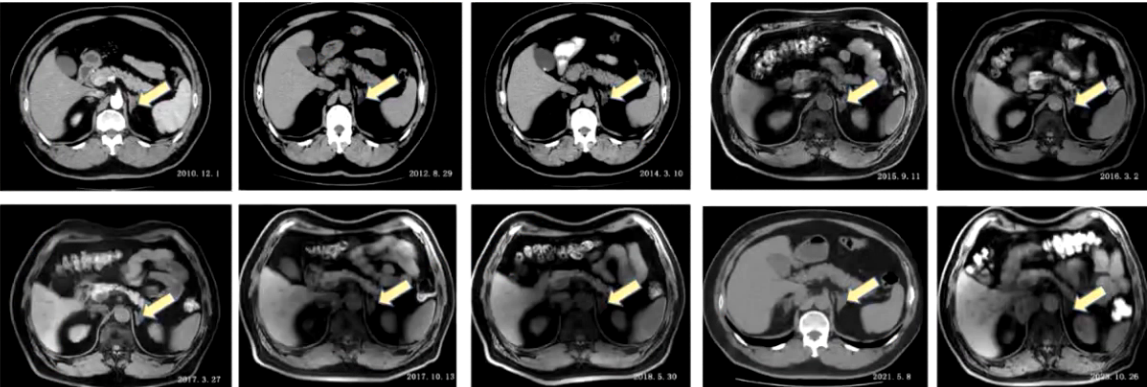

2) 入院前检查:2010年11月血钾4mmol/L,卧位肾素活性0.25ng/mL/h,醛固酮107pg/mL,立位肾素活性1.1ng/mL/h,醛固酮141pg/mL,卡托普利试验未被抑制,去甲肾上腺素0.682pmol/mL,肾上腺素0.03pmol/mL,多巴胺0.121pmol/mL,24小时尿香草苦杏仁酸(VMA)19.6mg。腹部增强CT提示双侧肾上腺结节影,多发腺瘤,右侧1.6cm×0.9cm,左侧0.8cm×0.8cm,不除外合并双侧肾上腺增生。垂体MRI未见异常,考虑原发性醛固酮增多症可能性大。因双侧肾上腺腺瘤,行双侧肾上腺静脉取血术,考虑采血并不在位,患者要求保守治疗,予硝苯地平控释片、螺内酯、氯沙坦钾控制血压,后调整降压方案为硝苯地平控释片、螺内酯、酒石酸美托洛尔片,血压控制在130/70mmHg左右。此后定期复查影像检查,双侧肾上腺腺瘤变化不大。

3) 病情转折:入院前两个月,患者自觉偶有头痛,夜尿增多,近半年体重下降10kg。2023年10月17日复查,肾素水平119.6pg/mL,醛固酮65.3ng/dL,24小时尿香草扁桃酸(VMA)14.45mg/24h,较起病初期明显增高。肾上腺MRI显示双侧肾上腺多发结节,较前变化不明显,胆囊结石较前增大,右侧膈肌脚旁肿块4.3cm×2.6cm较前增大。患者以“肾上腺占位及膈肌脚旁占位”收入院。

1) 病因探寻:患者此次血压波动,既往原发性醛固酮增多症诊断明确。血儿茶酚胺提示甲氧基去甲肾上腺素2026.6pmol/L、甲氧基肾上腺素792.6pmol/L,均超过参考范围。肾上腺CT提示右侧肾上腺内侧下腔静脉与右侧膈肌之间肿块影4.3cm×2.6cm,考虑神经源性肿瘤,原有双侧肾上腺多发腺瘤仍存在。PET-CT检查提示双侧肾上腺多发低密度结节,部分代谢活性增高,为功能性腺瘤,右侧膈肌角旁代谢活性增高的软组织密度肿块性质待定,不完全除外低度恶性肿瘤可能。结合患者右侧膈肌脚旁占位逐年增大、体重减轻、周围循环充盈欠佳、体位性低血压、血尿儿茶酚胺指标升高,考虑副神经节瘤为此次病情变化主要原因。